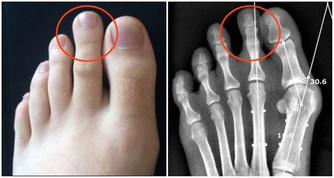

1. 身體健康管理:均衡飲食與規律運動

健康的身體是自我照護的基礎,良好的飲食與運動習慣能讓身體保持最佳狀態。